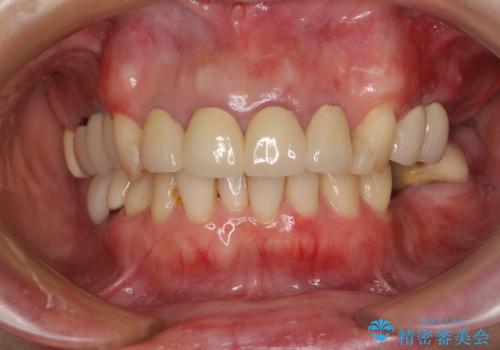

- 仮歯装着後に放置してしまい、恥ずかしいとのことで来院された患者様です。

仮歯が不適合で歯肉が腫脹していたため、しっかりと調整した新しい仮歯にして腫れを改善した上で、オールセラミッククラウンにて補綴することとしました。

日頃の歯磨きをしっかりと行ってくださるので、新しい仮歯に変えてから速やかに歯肉の状態が改善されました。

歯肉からの出血がほとんどないため精度の良い型取りができ、非常に適合の良い補綴治療を行うことができました。